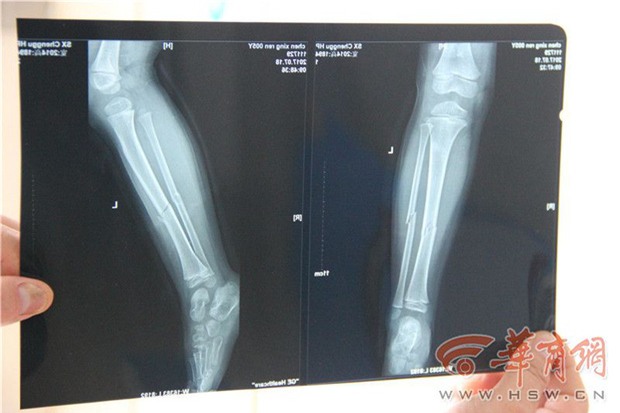

Vết thương nghiêm trọng của bé Minh Minh.

Ông Trương - người chứng kiến vụ việc cho biết: "Hôm đó tôi bán dưa hấu ở giao lộ thì thấy có một cậu bé từ trong chợ chạy ra, vừa đến ven đường thì bị xe máy đâm". Ông cho biết đó là một chiếc xe màu đỏ. Khi vụ tai nạn xảy ra, chân trái của cậu bé đều bị chèn bởi cả hai bánh xe.

Cũng là người chứng kiến vụ việc, bà Vương nói: "Tôi chạy ra xem thì thấy chân trái của thằng bé đã nhũn ra, không thể đứng lên được, chắc là gãy xương rồi". Lúc đó mặt đứa bé toàn là máu, cánh tay cũng bị thương, nằm trên đất khóc to trong đau đớn, không ngừng đòi tìm mẹ, còn nói mẹ bán hàng ăn ngay gần đây, nhưng mọi người xung quanh không ai quen cậu bé cả. Bà nói: "Nếu mà biết là con cháu nhà nào thì chúng tôi nhất định đã gọi người nhà đến rồi". Nhìn thấy vết thương nghiêm trọng của cậu bé, bà cùng những người xung quanh cũng khuyên người lái xe mau chóng gọi 120, đồng thời lập tức đưa đến bệnh viện.

Cũng trong chiều hôm qua, phóng viên đã đến thăm bé Minh Minh ở khoa chỉnh hình của Bệnh viện Nhân Dân huyện Thành Cố. Hiện, bé đang hồi phục khá ổn định. Với sự chăm sóc của gia đình, bé cũng đã dần dần cử động lại được. Theo phóng viên, bé Minh Minh ngoài chân trái bị gãy ra, vết thương trên mũi cũng đã đóng vảy, trên cánh tay và chân vẫn còn sẹo. Tinh thần của bé có vẻ đã khá hơn nhiều, chỉ chăm chú chơi đồ chơi, dường như đã quên mất cái đau. "Chú đi xe máy nói rằng sẽ đưa cháu đi tìm mẹ rồi sẽ đi khám bệnh, rốt cuộc lại nhét cháu vào thùng rác, rồi lại bỏ cháu trong đống rác rồi đi mất"- bé Minh Minh kể lại.